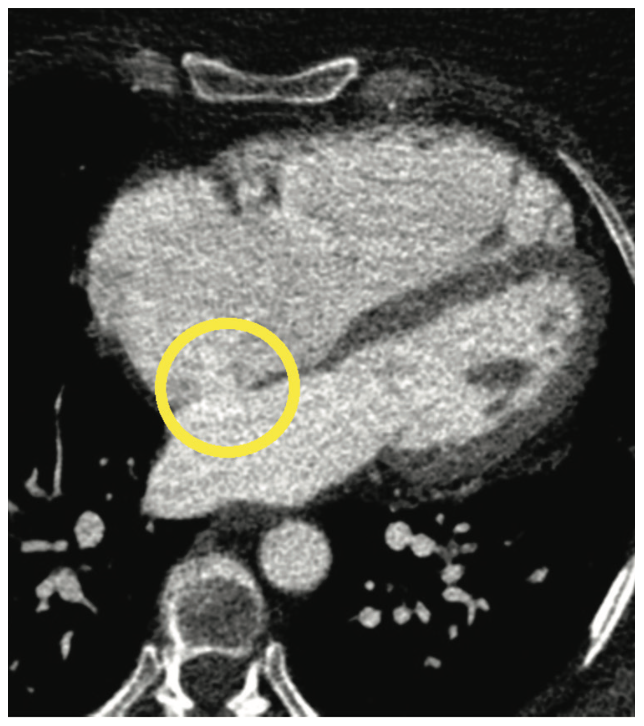

A gated cardiac CTA (structural/functional heart) is an increasingly viable imaging option for left atrial appendage occlusion, congenital heart disease, atrial or ventricular septal defects (Figure 9), valvular disease and prosthetic valvular dysfunction, cardiomyopathies, or cardiac masses such as myxomas.14,15 To perform a structural/functional heart scan, the CCTA and CT cardiac scoring scan protocols are used. The difference is the injection timing and setup with the dual-head syringe power injector. The objective is to allow segmentation and analysis of all cardiac chambers, as well as the coronary artery visualization. Functional or structural cardiac imaging allows for visualization of any atrial or ventricular septal defeats, as well as any cardiac masses, tumors, metastatic disease, thrombi, and vegetation.

The goal of this protocol is to enhance both sides of the heart equally. The motion of the left and right coronary arterial system differs in most patients, with right coronary artery (RCA) motion being greater. The split bolus IV contrast technique, specifically the 40:60 normal saline-to-contrast mix, minimizes artifact from high concentrations of IV contrast on the right side of the heart, while the first phase focuses on the right side. The advantage to this protocol is how it maintains enhancement on the left side of the heart and the coronary arteries, while improving the right side for IV contrast opacification.